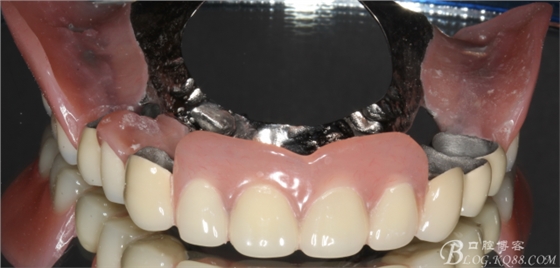

上頜基牙比較分散,選擇 5顆基牙的套筒冠修復(fù),

鈷鉻合金金屬內(nèi)冠

套筒冠外冠

修復(fù)后效果圖,